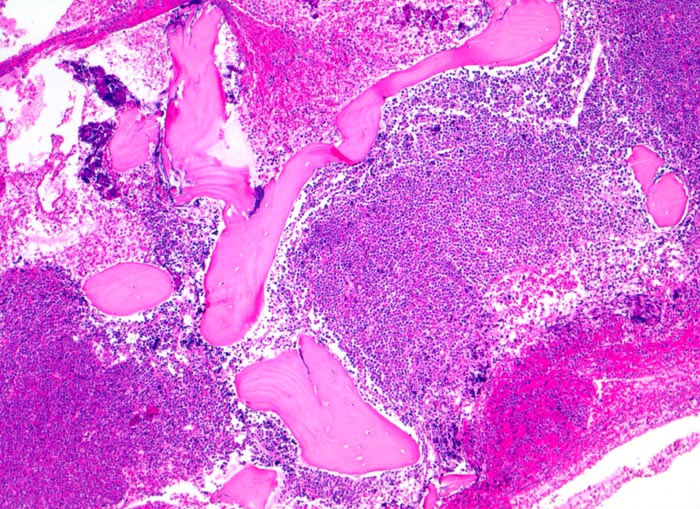

PathoPic ID 4021 - Akute lymphatische Leukämie (ALL)

Akute lymphatische Leukämie (ALL)

Knochenmark, Beckenkamm

Verdrängung des Fettmarkes durch diffuse Tumorzellrasen ohne Zerstörung der Knochenbälkchen.

Vergrösserte Lymphknoten, Hepato-Splenomegalie. Knochen- und Gelenkschmerzen, vermehrte Müdigkeit.

Histologie

50

13

männlich